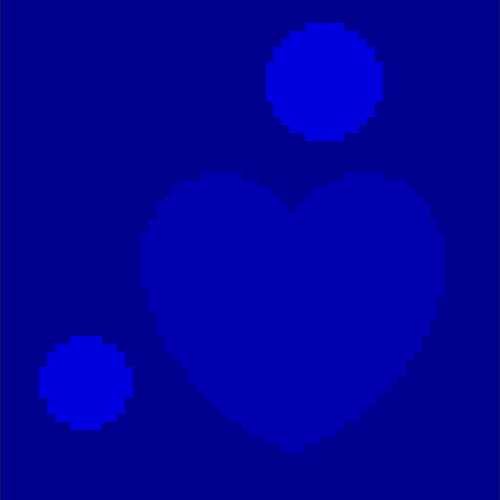

The first data set consists of a heart-shaped region and three circles on a static background (see figure 1 (a)). The two smaller circles are assumed to belong to

the same tissue type and therefore to the same subregion, which causes a total of four subregions, including the background. To simulate a more realistic application of dynamic SPECT

imaging, we used a synthesized representation of a rat liver as a second data set (see figure 1 (b)). The temporal concentration curves used to simulate the data sets

are shown in figure 2. As before, the total number of subregions was chosen to be equal to four in order to provide a both simple and realistic shape model.